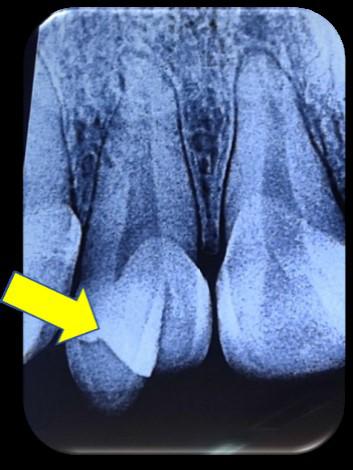

Se solicita una radiografía periapical, en la misma se observa la presencia del conducto radicular único, ancho con una sola cámara pulpar, está misma

ubicada en la corona mesiopalatina, también se puede observar la imagen radiopaca que evidencia la cúspide en garra (Fig.2).

Figura Nº2. Radiografía periapical que muestra que la pieza dentaria presenta una sola raíz y un solo conducto radicular, además presenta la imagen radiopaca de la cúspide en garra.

Fuente: Elaboración propia, septiembre 2021.